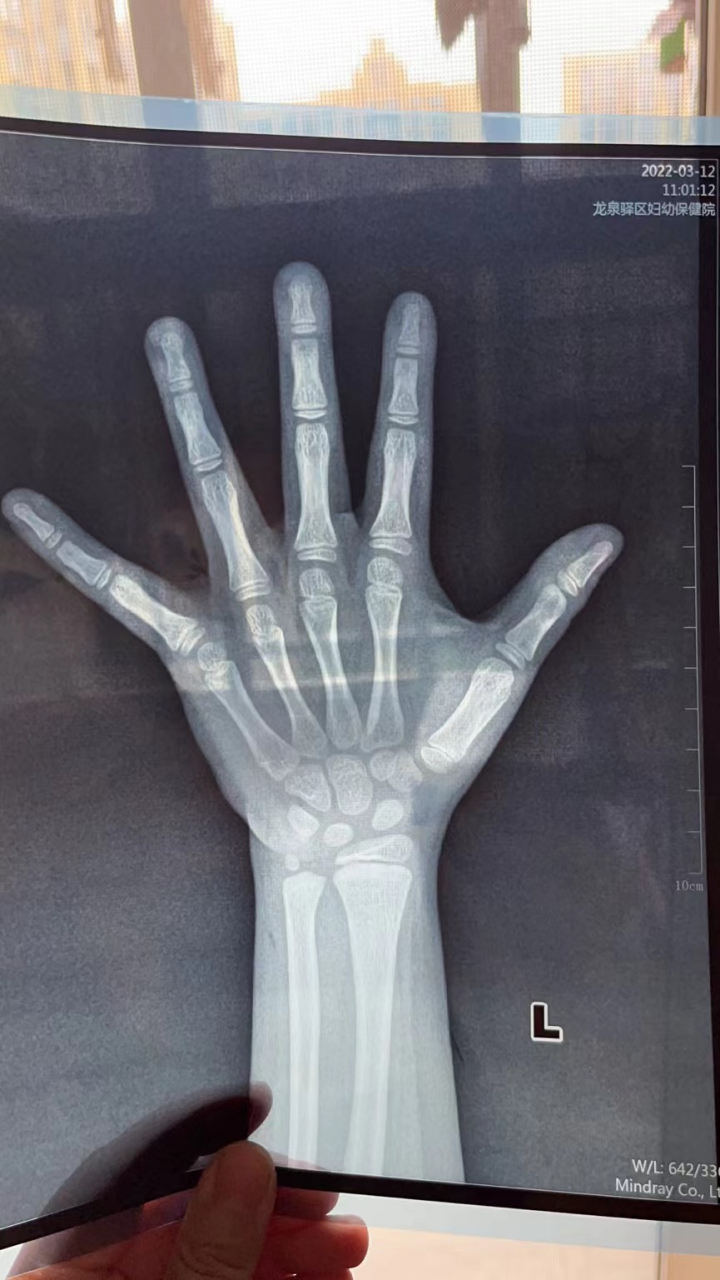

左手骨龄片